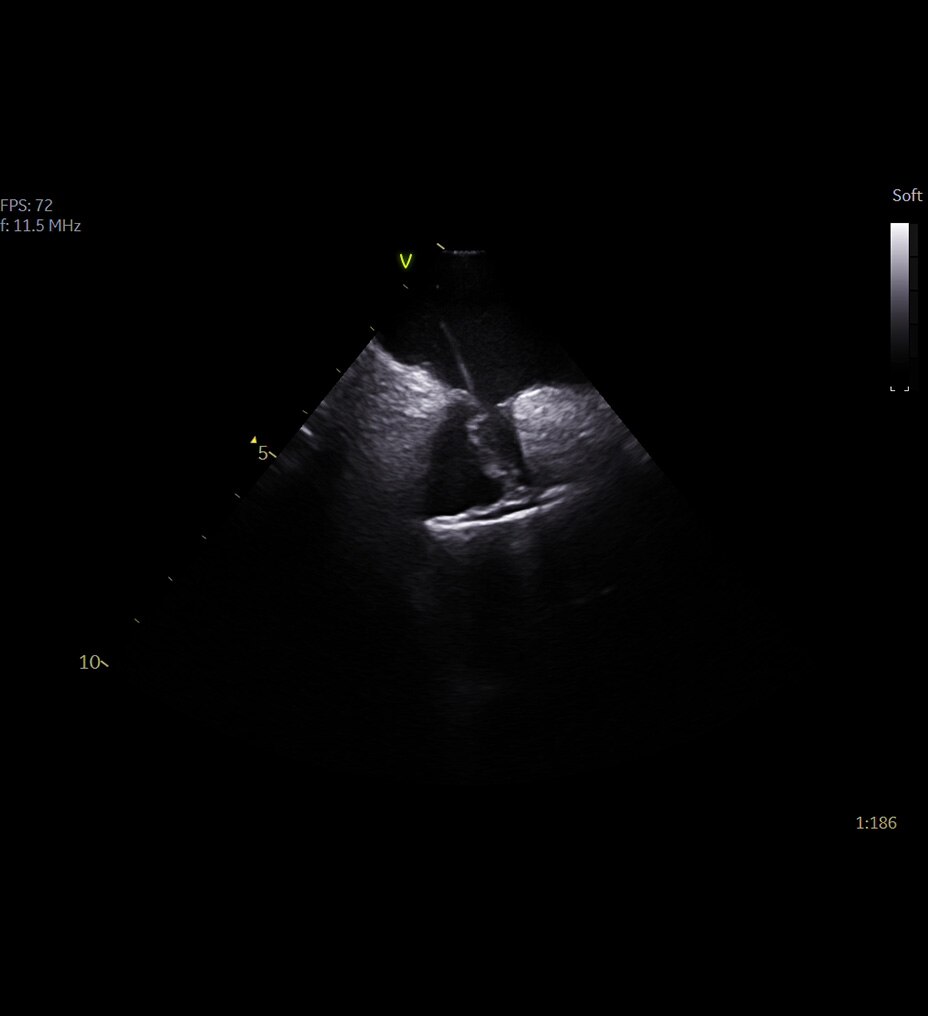

Alimentado por la tecnología SignalMax™, para que no tenga que comprometer la calidad de la imagen para la portabilidad